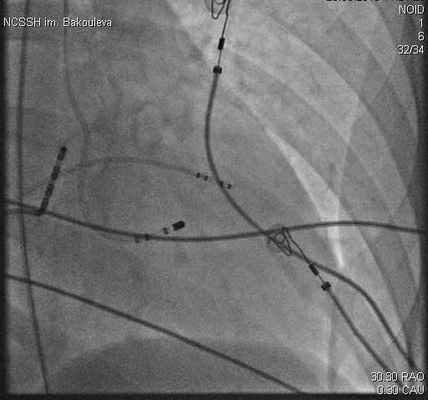

Рисунок 3. Правая косая проекция. Рентгенограмма, иллюстрирующая расположение аблационного электрода в левом желудочке. Аблационный электрод (ABL) позиционирован в задненижнем отделе МЖП. Диагностический четырехполюсный электрод (RVA) в верхушке правого желудочка. Диагностический десятиполюсный электрод в коронарном синусе (CS).

В данной зоне, локализующейся в задненижнем отделе левой поверхности межжелудочковой перегородки, в области задней ветви левой ножки пучка Гиса, выполнено 4 радиочастотных воздействия с удовлетворительными параметрами (мощность - 30-45 Вт, температура - 55-65 С, сопротивление - 105-115 Ом), длительностью по 60 с. – с положительным эффектом.

Выполнена программированная и учащающая стимуляция левого желудочка, при которой желудочковую тахикардию индуцировать не удалось. На этом процедура завершена.